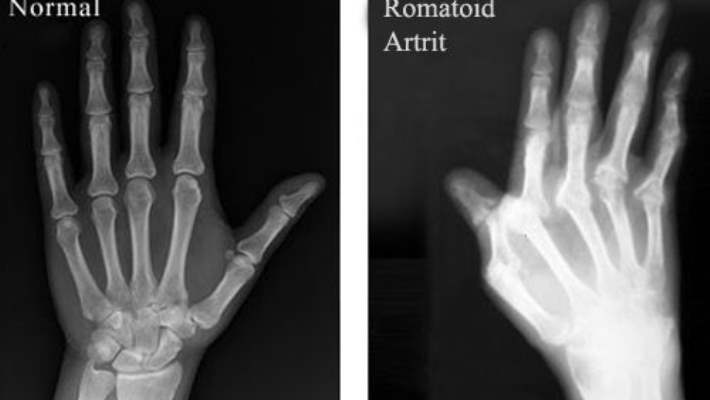

Röntgen genel olarak kıkırdak kaybını ve çekmiş eklemleri açığa çıkararak osteoartrit teşhisinde kullanılır. Bazen kan tahlilleri ve eklem aspirasyonu (test için eklemden küçük bir sıvı numunesi almak üzere bir iğnenin kullanılması) diğer artrit türlerini elemek için kullanılır. Doktorunuz bir başka hastalığın bir sonucu olarak bulaşıcı artritten şüphelenirse etkilenmiş eklemden alınan sıvı örneğinin tahlili, genellikle teşhisi doğrulamaya yardımcı olur.